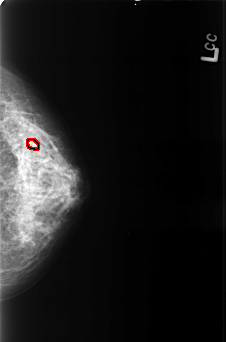

B_3426_1.LEFT_CC

LEFT_CC LINES 4440 PIXELS_PER_LINE 2936 BITS_PER_PIXEL 12 RESOLUTION 50 OVERLAY

FILE: B_3426_1.LEFT_CC.OVERLAY

TOTAL_ABNORMALITIES 1

ABNORMALITY 1

LESION_TYPE CALCIFICATION TYPE PUNCTATE-AMORPHOUS DISTRIBUTION CLUSTERED

ASSESSMENT 4

SUBTLETY 3

PATHOLOGY BENIGN

TOTAL_OUTLINES 1